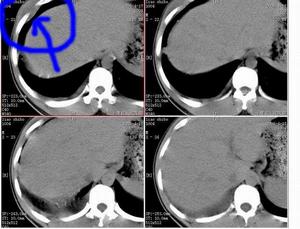

何杰金氏淋巴瘤CT圖HD的國際臨床分期(AnnArbor會議,1971)標準如下。